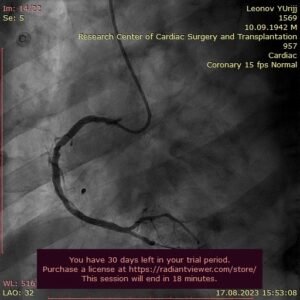

Бригадой врачей интервенционных хирургов Шералиева Есимхана, Сейсембекова Вадима, рентген лаборантов Гранкиной Оксаны, Хакимовой Зиеды, проведена Коронароангиография (КАГ). Выявлен атеросклероз коронарных артерий, кальцинированный протяженный стеноз огибающей артерии (ОА) до 99 %, а также мешотчатое аневризматическое расширение в пр/3 правой коронарной артерии (ПКА) размером 9,3х7,2 мм. Гигантская мешотчатая аневризма правой коронарной артерии оказалось случайной находкой при выполнении КАГ.

Достижение удовлетворительного результата подтверждено при контрольной КАГ. Состояние стент-графта правильное, остаточных стенозов, диссекций не выявлено.